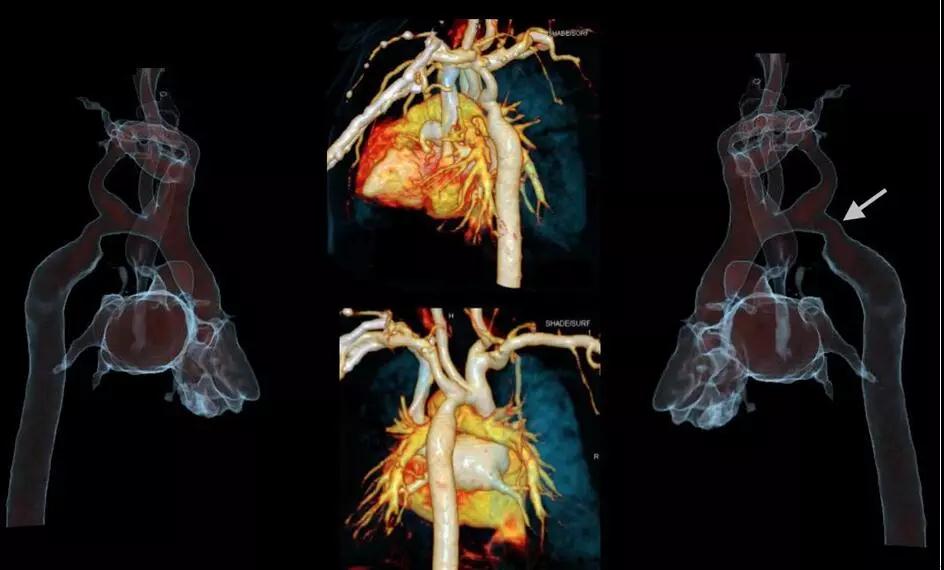

5.1秒一站式多血管同時掃描:

SOMATOMForce 開源CT的73.7厘米/秒的業內最快掃描速度,已突破血流方向相反的成像難題,使得CTA聯合掃描在血管成像領域應用研究將更加深入,未來低輻射和低對比劑量一站式多部位多血管CTA(頭頸冠脈成像、胸痛三聯征、心臟+腹部血管+下肢血管成像)將成為指導心臟和外周血管性疾病介入診療的重要工具。